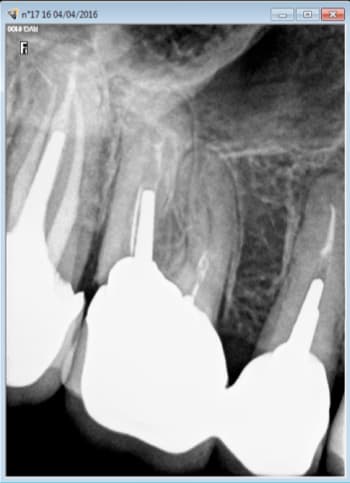

Comme celui ci cadre dans une grande entreprise avec une "bonne moutouelle" vu en urgence cette semaine suite à une bonne pèche sur 15-16 qui est reparti avec ca boite d'augmentin en attendant mieux. -)))

Capture d e cran 2016 04 08 12.08 - Eugenol

Capture d e cran 2016 04 08 12.09 - Eugenol

Capture d e cran 2016 04 08 12.23 - Eugenol

Enfin bon la 15 et la 16 je m'avance peut etre un peu. C'est possible que ce soit la 14 ou la 17 car en 2009 je ne mettais pas la digue et je ne condensais pas au mac spadden ( d'ailleurs ca c'est susceptible de constituer un indu car ca ne respecte pas les recommandations HAS lol !) . Qu'en pensez vous ? -))))